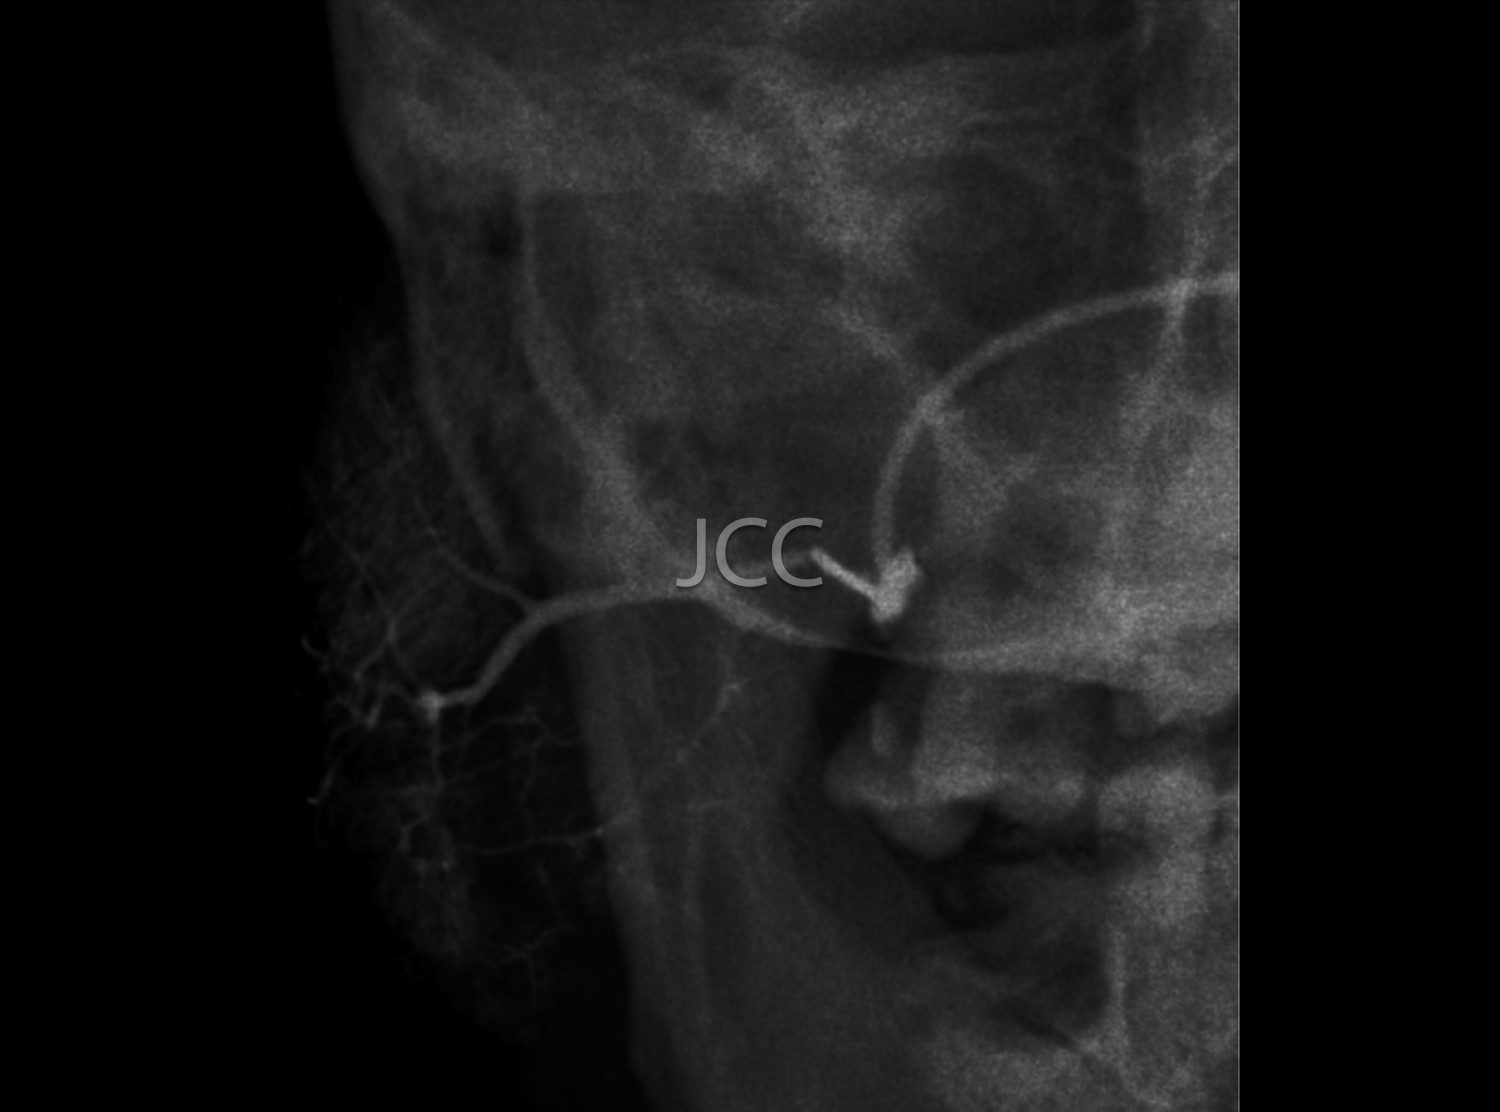

Dental Radiology - Sialography

Sialography is a minimally invasive complementary means of diagnosis consisting of the introduction of a contrast product through the parotid or submandibular glands duct and in the performing of a series of radiographs of the salivary gland to be studied.